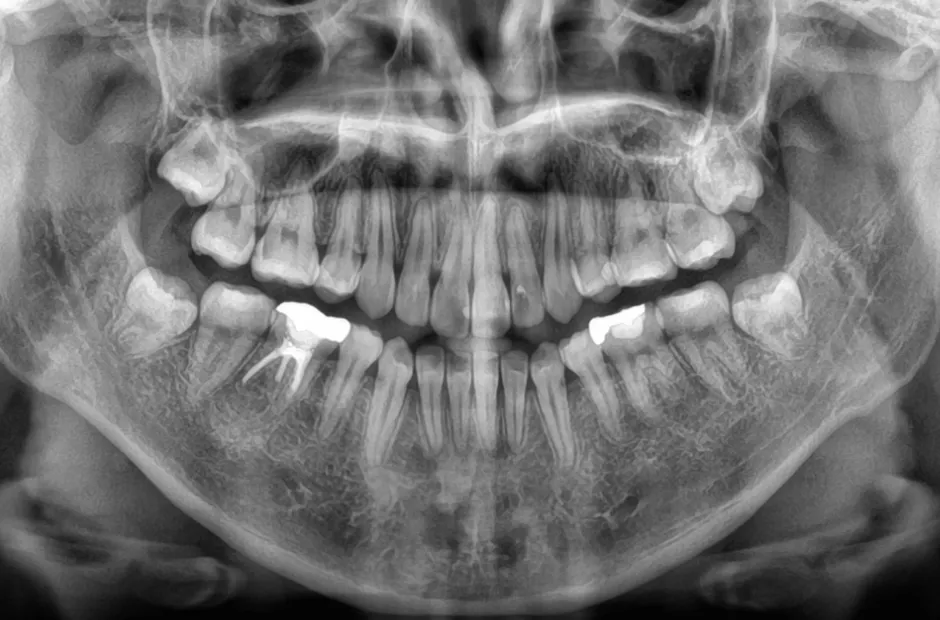

先天欠如

| 診断名・主訴 | 先天欠如 |

|---|---|

| 年齢・性別 | 14歳・女性 |

| 治療期間・回数 | 2年 |

| 治療に用いた主な装置 | ブラケット矯正 |

| 抜歯部位 | なし |

| 治療費 | 60万円(税抜) |

| リスク・副作用 | 装置による違和感・疼痛・歯肉退縮・歯根吸収・虫歯のリスクなど |